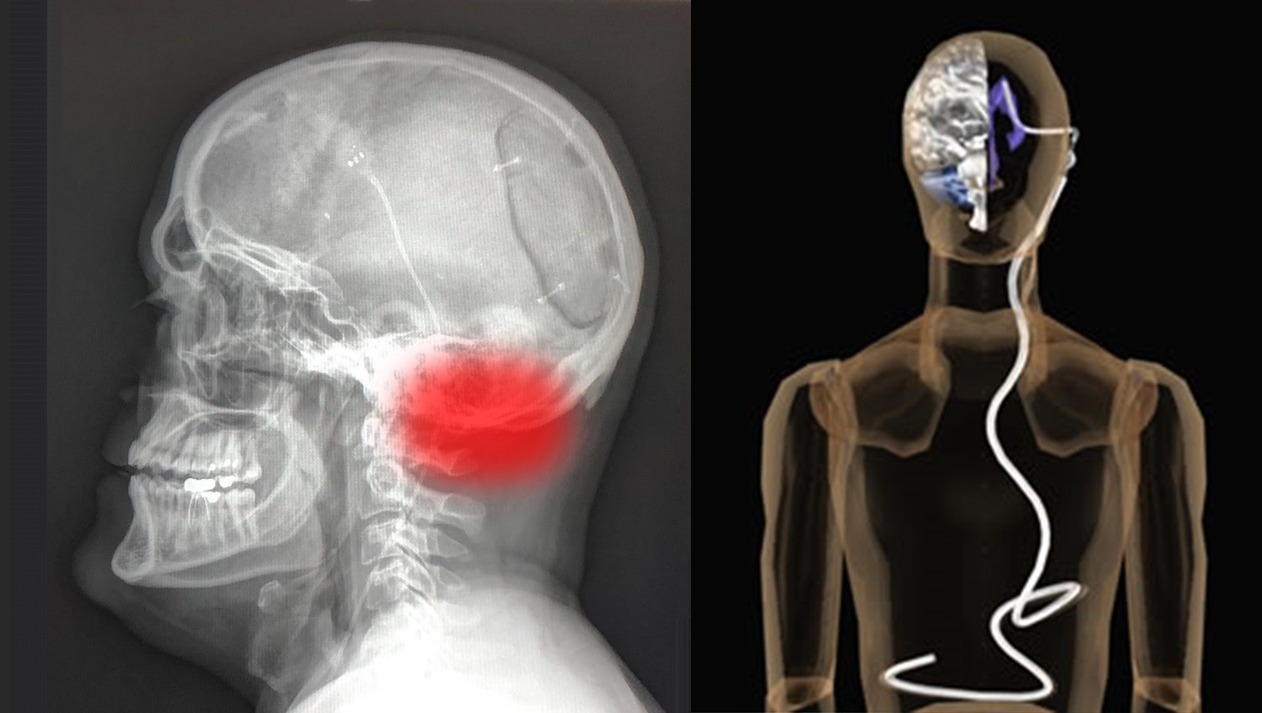

Eric is in the fight of her life, he has been diagnosed with a Glioblastoma Brain Tumor. Unfortunately the cancer is in his Brain Stem, his experimental treatment is not covered by the VA.

The VA Hospital teamed up with MD Anderson Hospital to perform a hemispherectomy, which is a rare surgery where 1/4th of his brain was removed.

4 ½ years later the cancer came back with a vengeance and began to grow within Eric’s Brain Stem. Within 4 months, the cancer went from a tiny dot to the size of a dime!

Eric has begun his treatment at the VA Medical Center at Houston, TX. As the Glioblastoma brain cancer is growing in his brain stem, pressure is building up causing various issues. Eric has developed the following issues: - Tunnel vision – head aches – weak legs - Short term memory loss – and more…